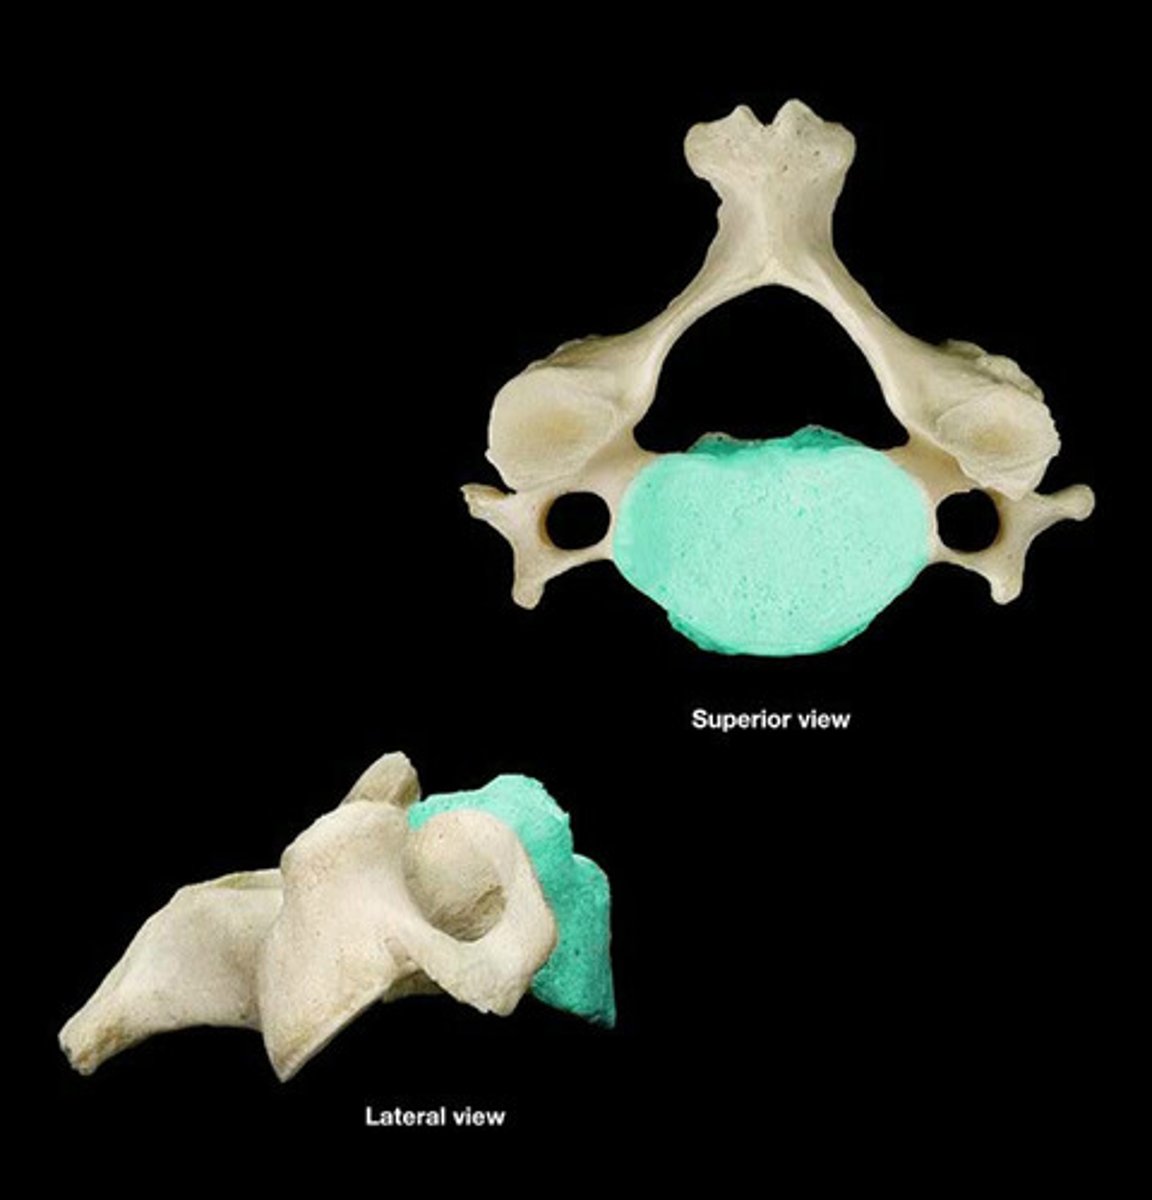

Vertebral Body

Vertebral Arch

Vertebral Foramen

Spinous Process

Transverse Process

Transverse Foramen